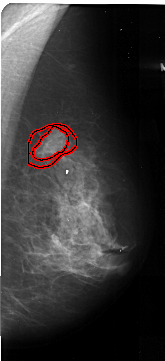

FILE: A_1035_1.RIGHT_MLO.OVERLAY

TOTAL_ABNORMALITIES 1

ABNORMALITY 1

LESION_TYPE MASS SHAPE IRREGULAR MARGINS SPICULATED

ASSESSMENT 5

SUBTLETY 5

PATHOLOGY MALIGNANT

TOTAL_OUTLINES 2

BOUNDARY

CORE